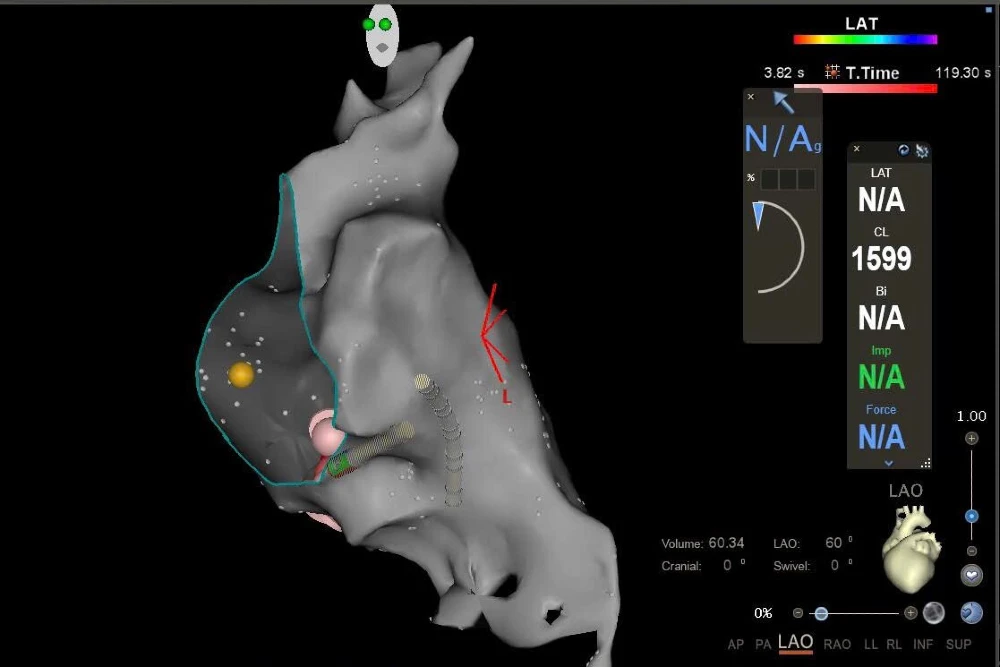

Các catheter xoang vành và các buồng tim được dựng hình lại như hình vẽ, và tiến hành tìm đường dẫn truyền phụ bằng kinh nghiệm suy luận giải phẫu tim và không gian 3D.

Tại vị trí thành sau của vòng van 3 lá chúng tôi ghi nhận điện thế bất thường của đường dẫn truyền phụ. Tiến hành cắt đốt vị trí này chấm dứt hoàn toàn đường dẫn truyền phụ và bệnh nhân không còn những cơn nhịp nhanh bất thường nguy hiểm.

Hệ thống mapping 3D Carto giúp dựng hình buồng tim và xác định nhanh vị trí ổ loạn nhịp ở thành giữa vách buồng tống thất (P). Đặc biệt hơn, chúng tôi đưa vào sử dụng catheter cắt đốt có cảm biến lực (Smart touch) là một trong những catheter cắt đốt tiên tiến nhất hiện nay.

Cụ thể, cảm biến lực trên đầu catheter sẽ biểu thị lực áp của catheter trong buồng tim cũng như các hướng xoay được biểu thị màu và mũi tên được biểu hiện liên tục lên màn hình giúp cho các bác sĩ di chuyển catheter và điều chỉnh độ áp được dễ dàng.